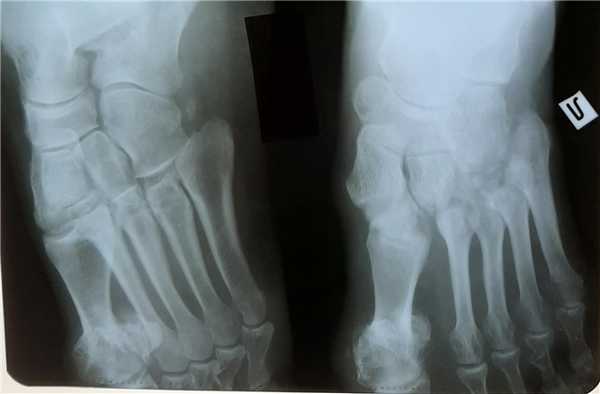

Для инструментальной диагностики используются рентгенограммы с\без нагрузки в сравнении со здоровой стороной, при их малой информативности рекомендовано выполнение стресс-рентгенограмм, аналогично приведёному выше тесту на нестабильность.

При рентгенографии все снимки выполняются в сравнении со здоровой стопой. Существует несколько основных рентгенологических признаков повреждения сустава Лисфранка. 1. Отсутствие параллельности медиального края основания 2-й плюсневой и медиального края медиальной клиновидной кости 2. Расширение между основаниями 1 и 2 плюсневых костей 3. Наличие костного фрагмента в области основания 2-1 плюсневой кости 4. Тыльный подвывих на боковой проекции 5. Разрыв линии предплюсне-плюсневого сочленения.

У нашей пациентки произошёл гомолатеральный вывих, то есть все плюсневые кости сместились в наружном направлении. На стандартных рентгенограммах в свежих случаях данные повреждения пропускают практически в 100% случаев. Необходимо делать рентгенограммы обеих стоп стоя с нагрузкой весом тела и даже в такой ситуации неопытный глаз пропустит травму.

Лучше - сделать КТ исследование, где в сравнении со здоровой стороной будет очень хорошо видно повреждение.